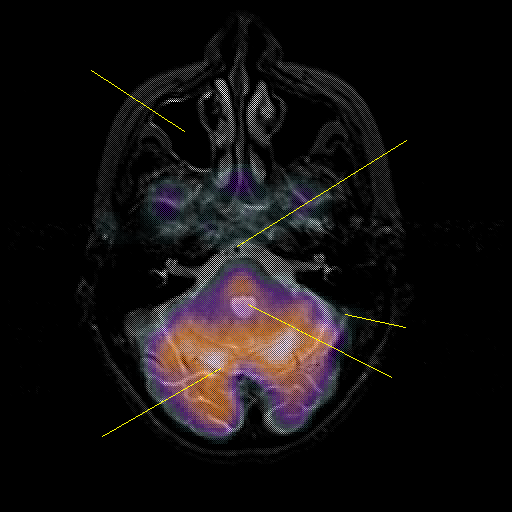

overlay : Slice 14

Slice 14

Pointers

Labeled